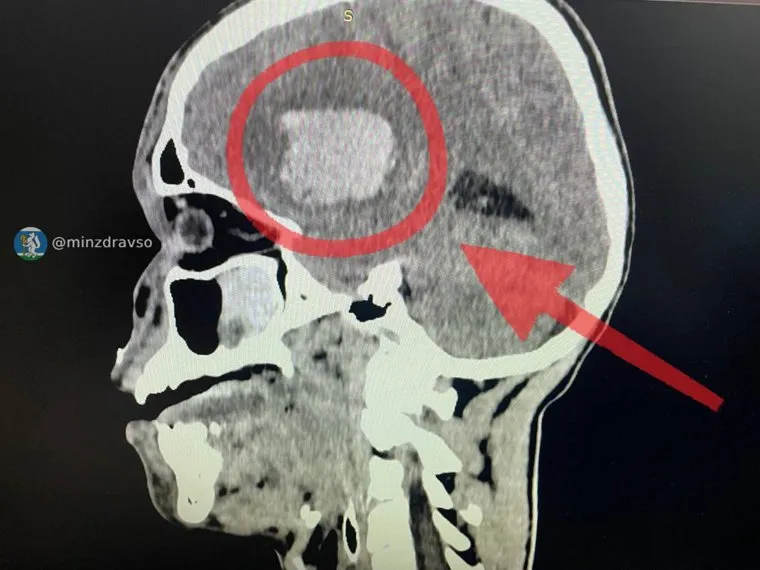

Медики из трех больниц Свердловской области провели срочную операцию 17-летнему подростку, получившему тяжелую травму головы в ДТП под Серовом. У пациента диагностировали внутримозговую гематому размером с теннисный мяч, сообщили в пресс-службе регионального минздрава.

«Счет шел на минуты. Процесс усугублялся нарастающим кровотечением, которое четко определялось при нейровизуализации. Комплексная бригада врачей провела декомпрессивную трепанацию черепа и удалила внутримозговую гематому размером с теннисный мяч», — пояснили там.